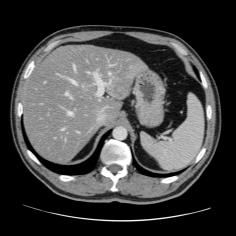

Manually segmenting the hepatic vessels from Computer Tomography (CT) is far more expertise-demanding and laborious than other structures due to the low-contrast and complex morphology of vessels, resulting in the extreme lack of high-quality labeled data. Without sufficient high-quality annotations, the usual data-driven learning-based approaches struggle with deficient training. On the other hand, directly introducing additional data with low-quality annotations may confuse the network, leading to undesirable performance degradation. To address this issue, we propose a novel mean-teacher-assisted confident learning framework to robustly exploit the noisy labeled data for the challenging hepatic vessel segmentation task. Specifically, with the adapted confident learning assisted by a third party, i.e., the weight-averaged teacher model, the noisy labels in the additional low-quality dataset can be transformed from "encumbrance" to "treasure" via progressive pixel-wise soft-correction, thus providing productive guidance. Extensive experiments using two public datasets demonstrate the superiority of the proposed framework as well as the effectiveness of each component.